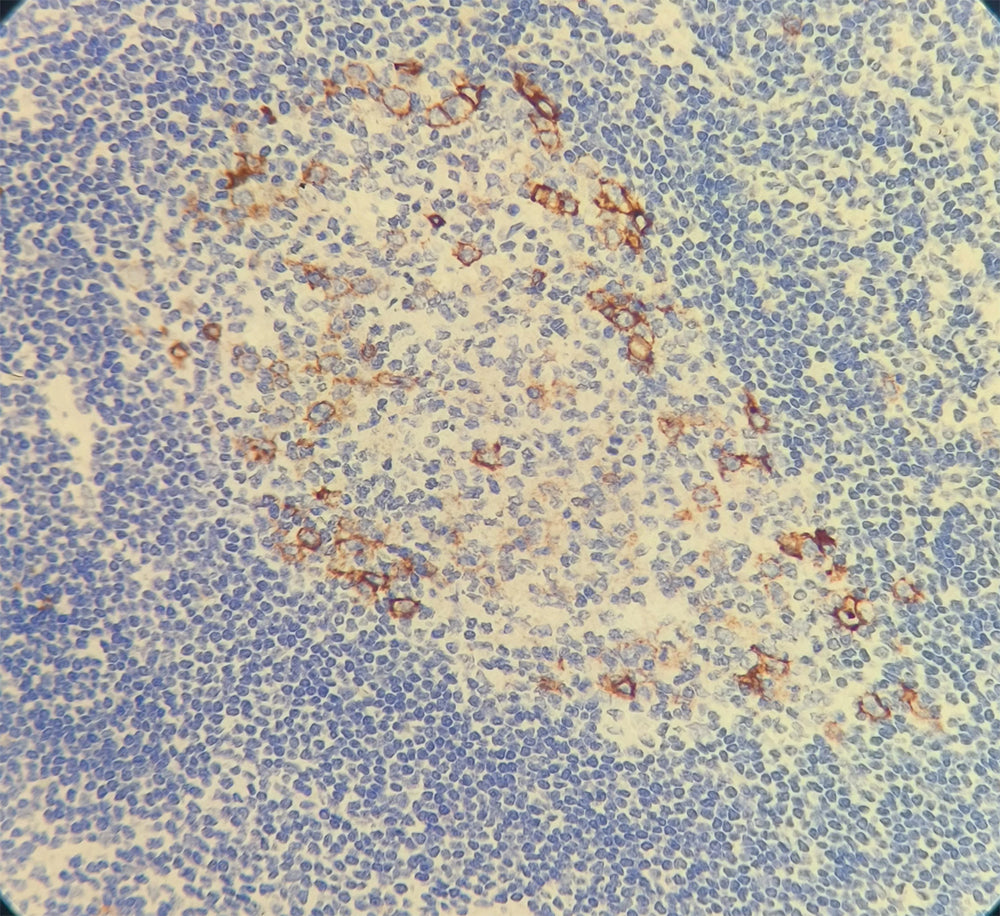

Contrôle positif : Tissu amygdalien